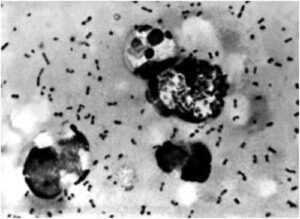

“Devo sottolineare che non c’è un singolo batterio dell’allergia,” spiega il professor Bisgaard. “Abbiamo studiato i batteri stafilococco e coli in modo approfondito e non c’è alcuna relazione. Quello che conta è venire a contatto con un gran numero di batteri diversi nelle prime fasi della vita, quando il sistema immunitario si sta sviluppando e sta “imparando”. Il periodo durante il quale il bambino è immaturo dal punto di vista immunologico e può essere influenzato dai batteri è breve e si conclude un paio di mesi dopo la nascita.”